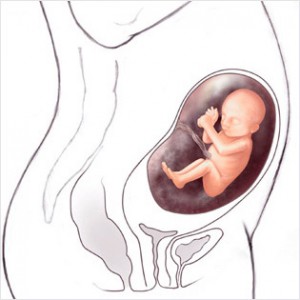

Bu haftadan itibaren artık bebek rahim içerisinde oldukça fazla yer kaplar ve bu yüzden ona hareket edecek fazla alan kalmaz. Eğer bebeğinizin hareketlerinde azalma his ederseniz endişe etmeyin, hareketlerin azalması bu yüzdendir.

Bebeğin Boyutu: 43.7 cm, 1.9 kg